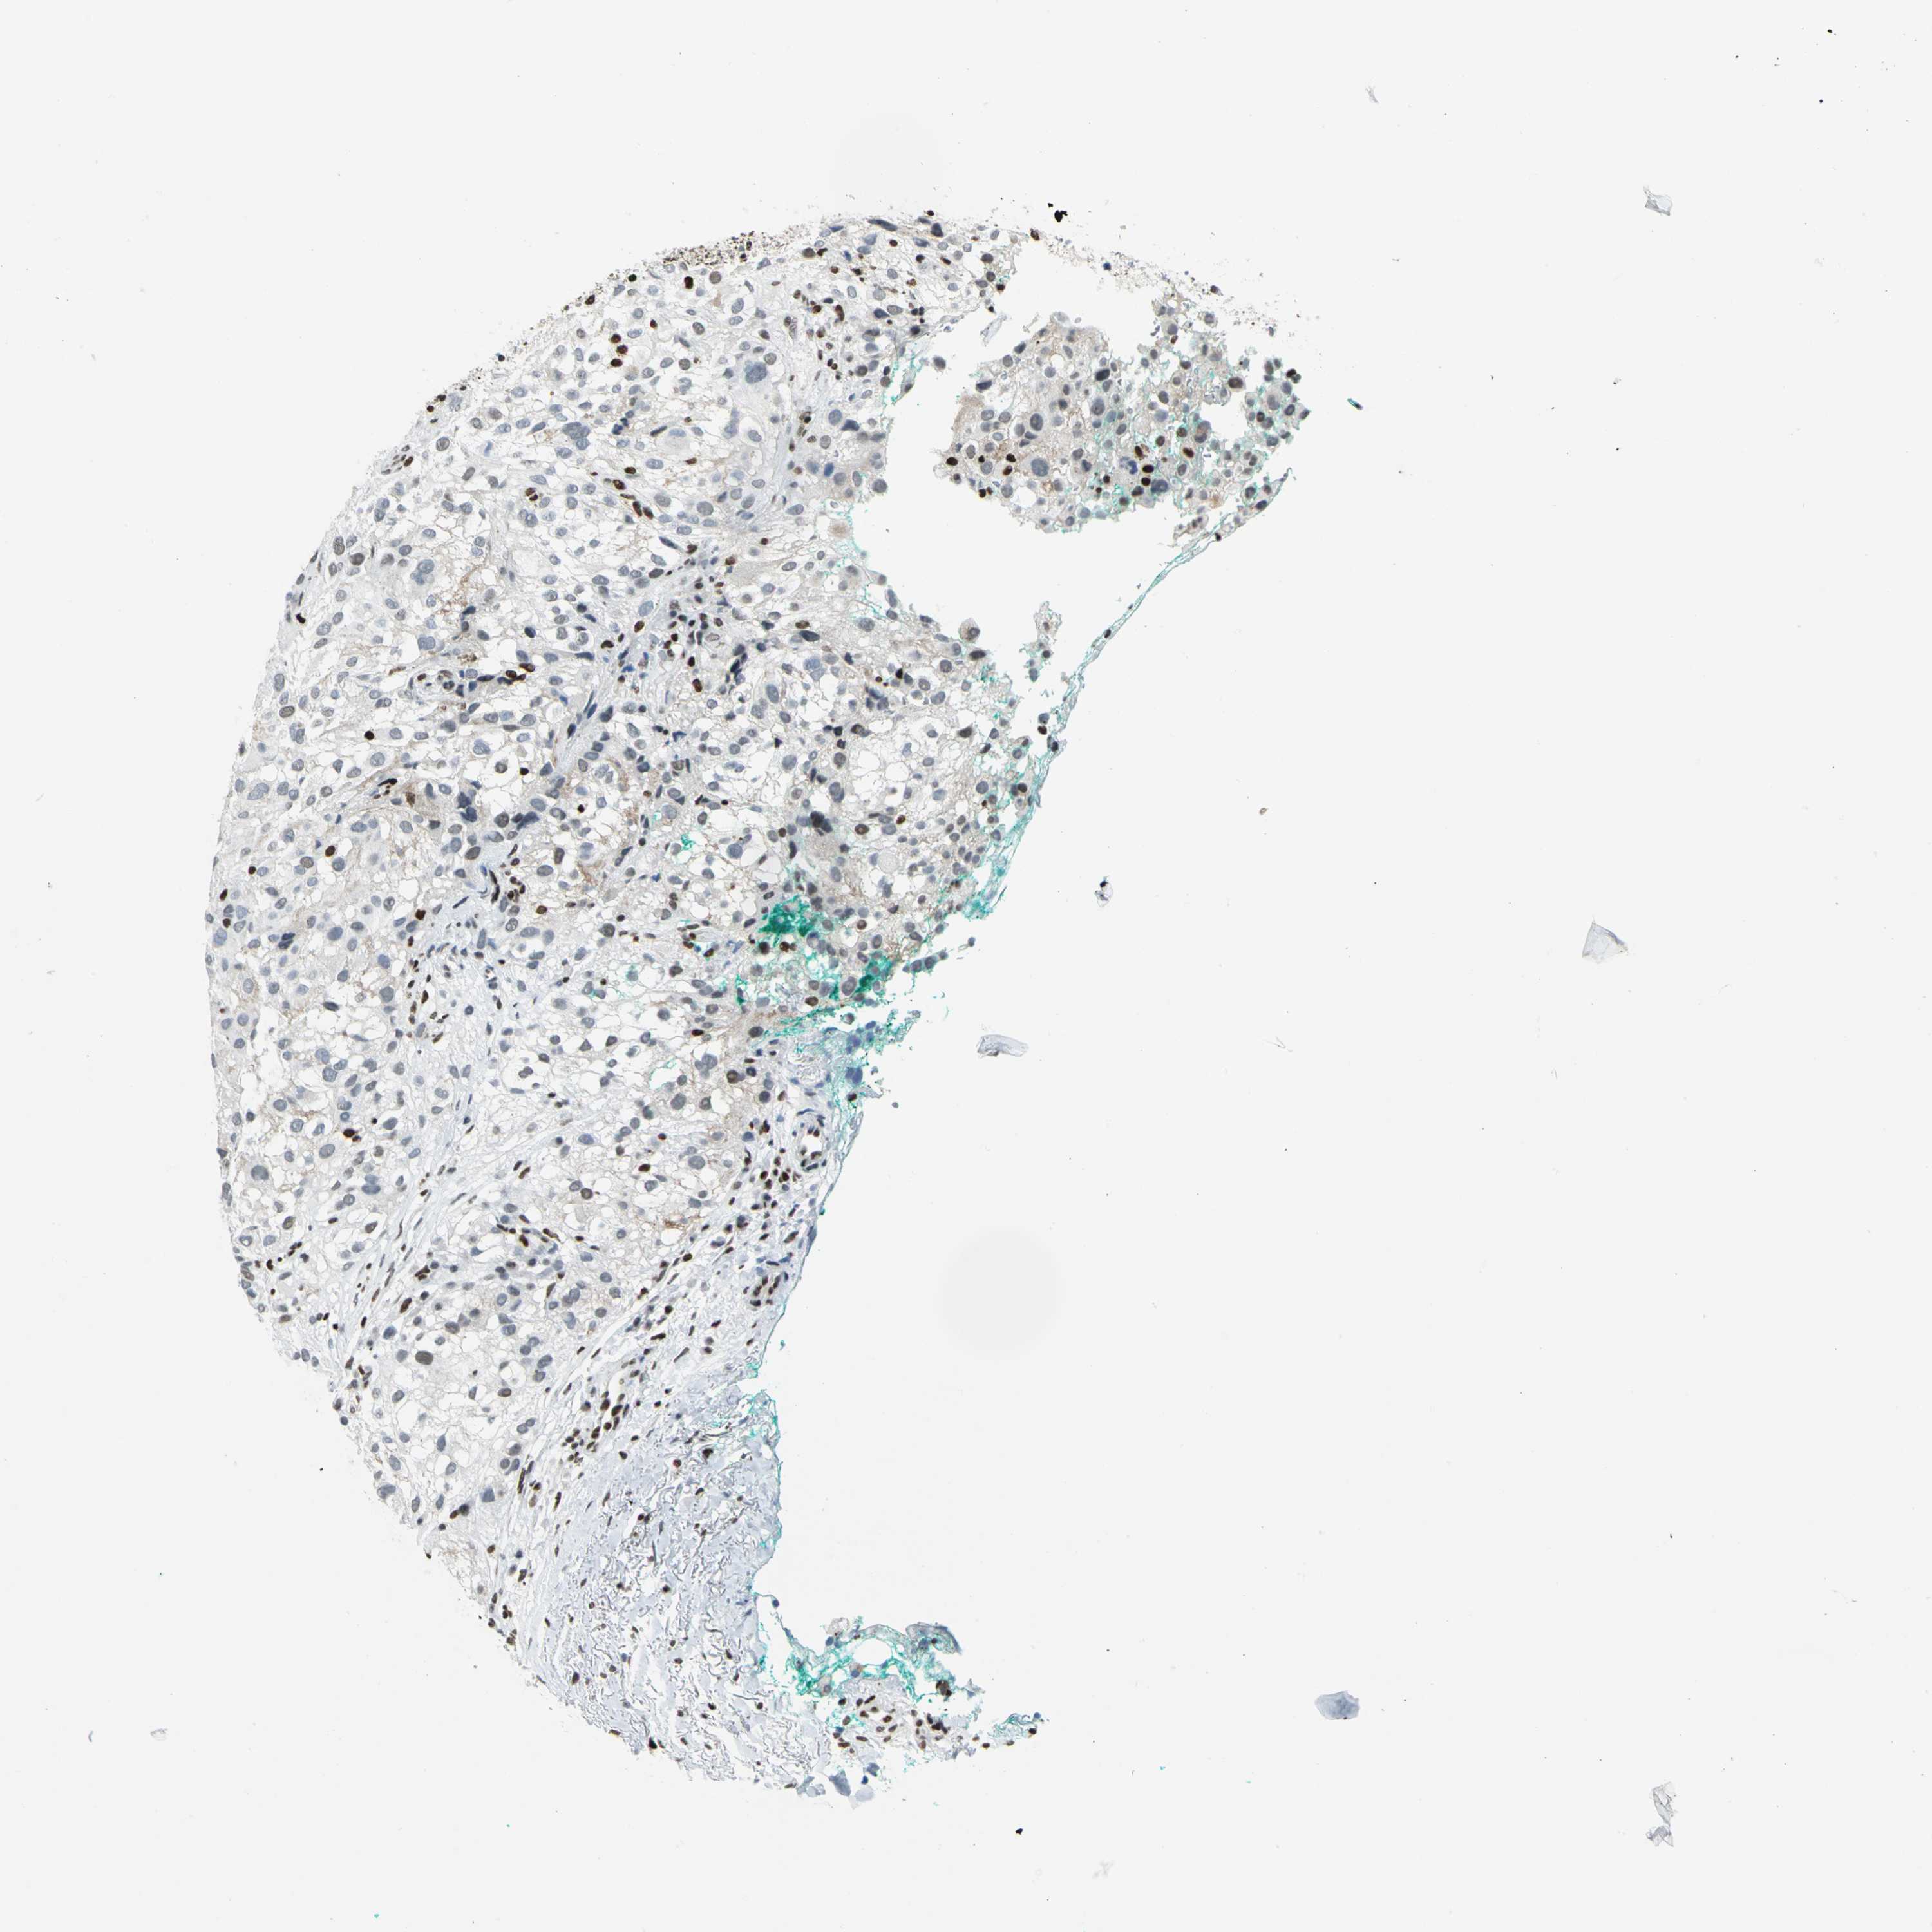

MELANOMA - Protein expressioni

A mouse-over function shows sample information and annotation data. Click on an image to view it in a full screen mode. Samples can be filtered based on level of antibody staining by selecting one or several of the following categories: high, medium, low and not detected. The assay and annotation is described here.

Note that samples used for immunohistochemistry by the Human Protein Atlas do not correspond to samples in the TCGA dataset.

Antibody stainingi

Antibody staining in the annotated cell types in the current human tissue is reported as not detected, low, medium, or high, based on conventional immunohistochemistry profiling in selected tissues. This score is based on the combination of the staining intensity and fraction of stained cells.

Each image is clickable and will lead to virtual microscopy that enables deeper exploration of all samples and also displays staining intensity scores, fraction scores and subcellular localization as well as patient and tissue information for each sample.

Antibody HPA004911

Staining

High

Medium

Low

Not detected

Intensity

Strong

Moderate

Weak

Negative

Quantity

>75%

75%-25%

<25%

None

Location

Nuclear

Cytoplasmic/membranous

Cytoplasmic/membranous,nuclear

Malignant melanoma, NOS

Malignant melanoma, Metastatic site